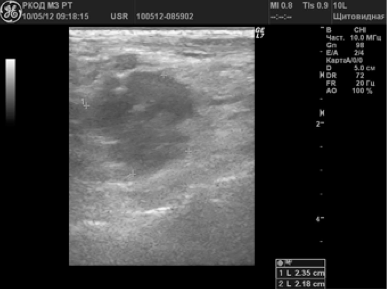

В 58 (38,2%) случаях было заподозрено метастатическое поражение лимфатических узлов. Измененные ЛУ имели размеры от 6 до 65 мм; 72,4% лимфатических узлов имели шарообразную форму, П/ПЗ2,0; 17,3% — неправильную форму в виде конгломератов. У 24 (41,4%) пациентов были выявлены единичные измененные лимфоузлы; у 34 (58,6%) — множественные. У 79,3% лимфоузлов отсутствовала дифференциация на кору и ворота; у 20,7% — ворота определялись в виде мелкого гиперэхогенного включения. 70,8% лимфатических узлов были гипоэхогенными (рис. 3); 12% — анэхогенными; 17,2% — неоднородную структуру с участками повышенной и пониженной эхогенности, с жидкостными включениями и кальцинатами (рис. 4).

Рисунок 4.

Метастатаз солидно-жидкостного строения в лимфоузле шеи